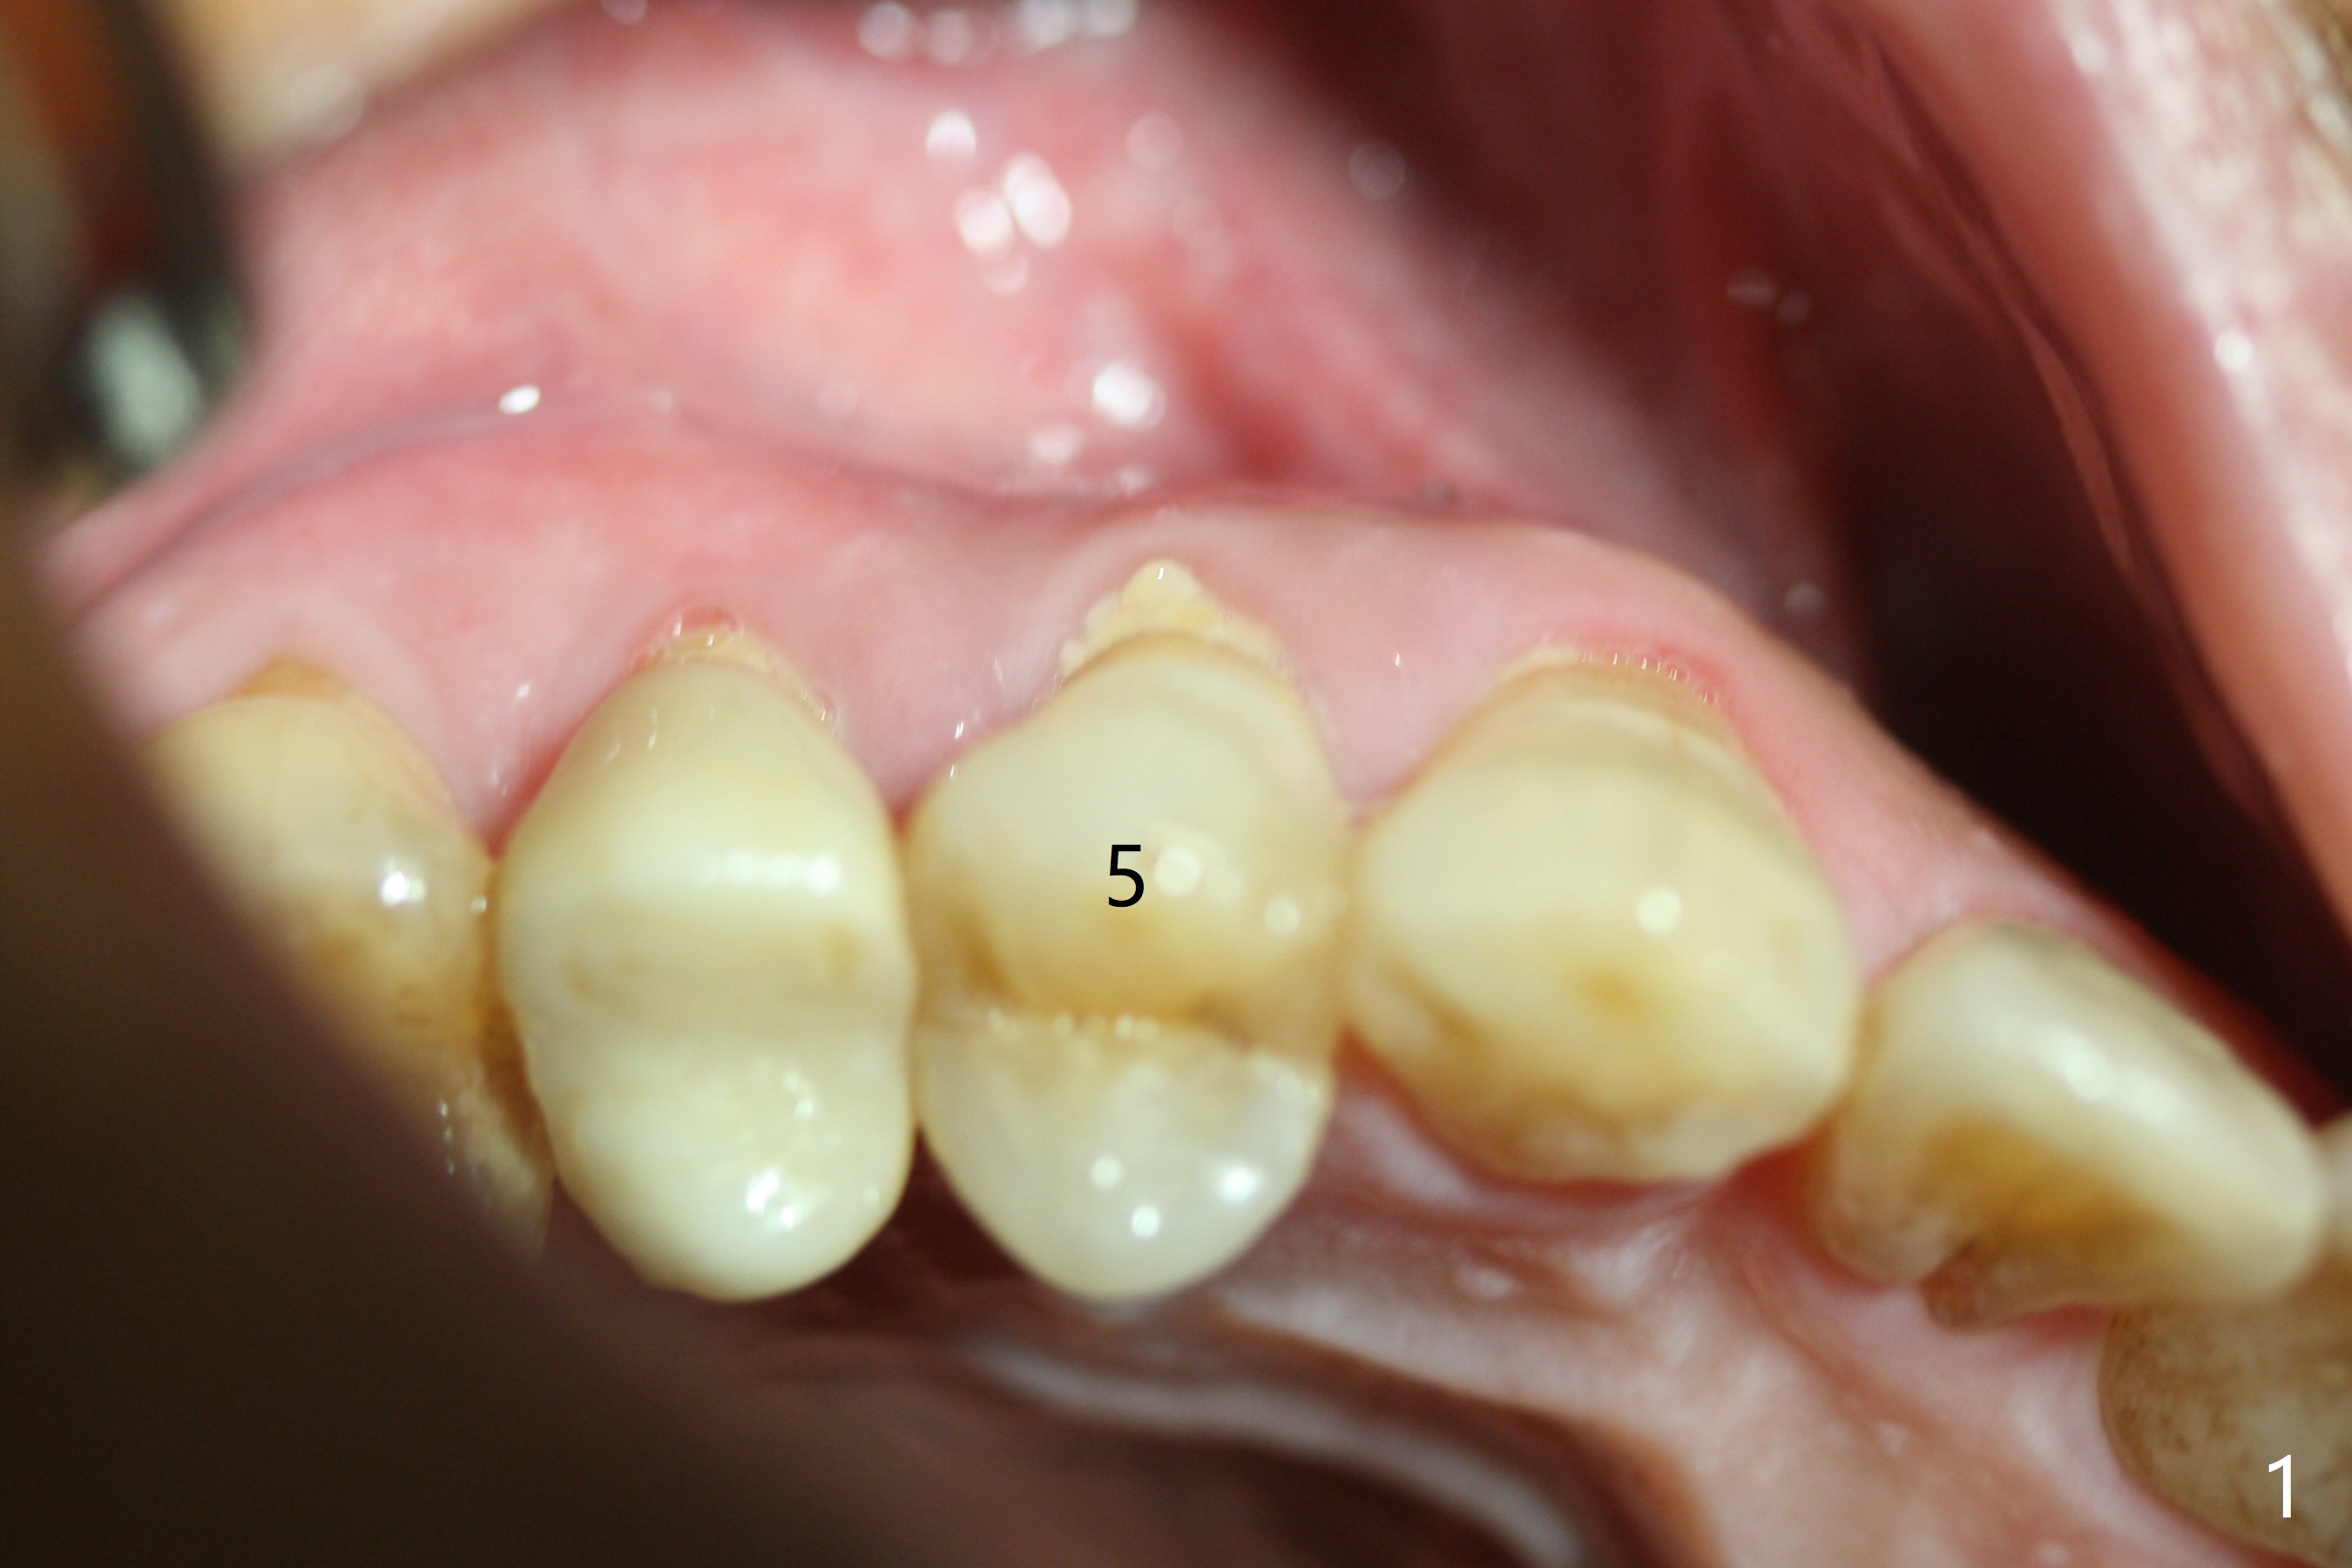

The buccal plate is normal at the tooth #5 (Fig.1) with the loose palatal fragment (Fig.2 P). Extraction leads to root fracture. Sectioning removes the palatal portion of the root and keeps the buccal semilunar piece (Fig.3 *); the mesiopalatal plate is resorbed (P). Initial osteotomy is off (Fig.4 (R: remaining root)). Redirection improves the trajectory (Fig.5). With the 2nd redirection (Fig.6 (4.5 mm tap)), a 4.5x12 mm implant is placed with 50 Ncm and sinus lift (Fig.7 black *); bone graft is placed with emphasis on the palatal defect (white *). As usual, an immediate provisional is fabricated. In fact the abutment may be not completely seated because of contact with the mesial crest. Prepare anesthetic and 5.5 mm profile drill. Take parallel BW or PA. Take occlusal photos to show no buccal or mesiopalatal atrophy. After 5.5 mm profile drill 11 months postop, the abutment has no contact with the mesial crest (Fig.8 <). Since the proximal contact between #3 and 4 is light with food impaction, the provisional at #5 is fabricated with tight distal contact. When the patient returns for final crown cementation (Fig.9), the food impaction is minimal between #3 and 4. The distal black triangle (Fig.10 *) and exposure of the abutment margin (^) are partially related to provisional fabrication and should dissolve over time considering socket shield.